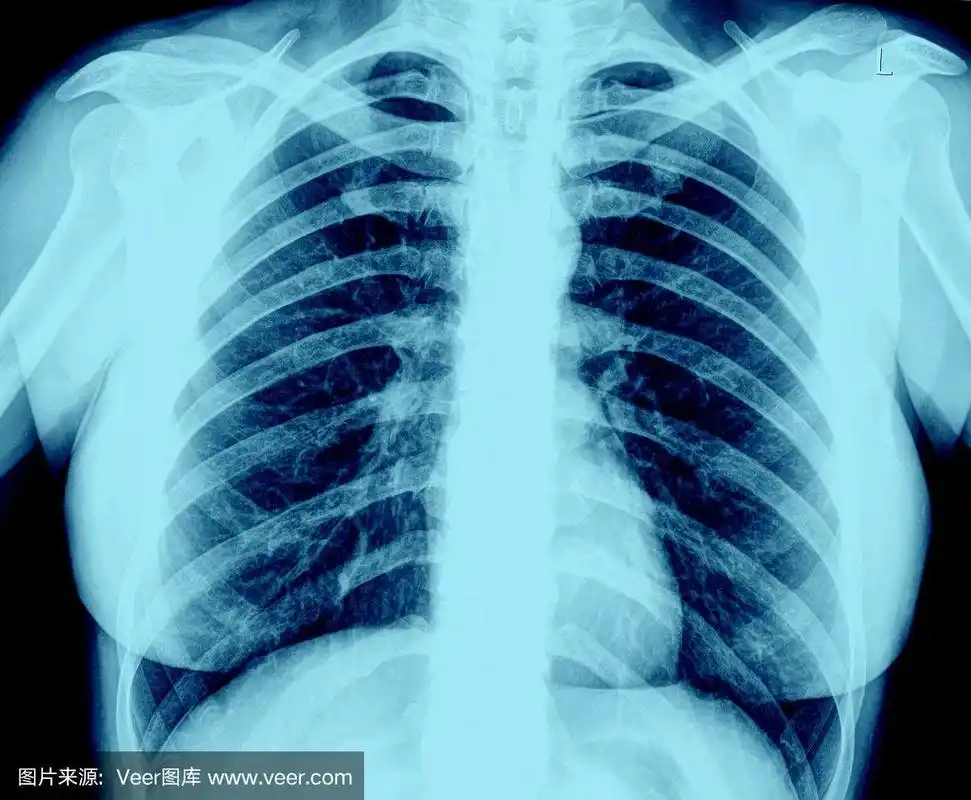

正常人的胸部

求助正常肺部x光片图片供教学用

肺部x射线图像

肺部x光

肺部正常和x线异常表现ppt